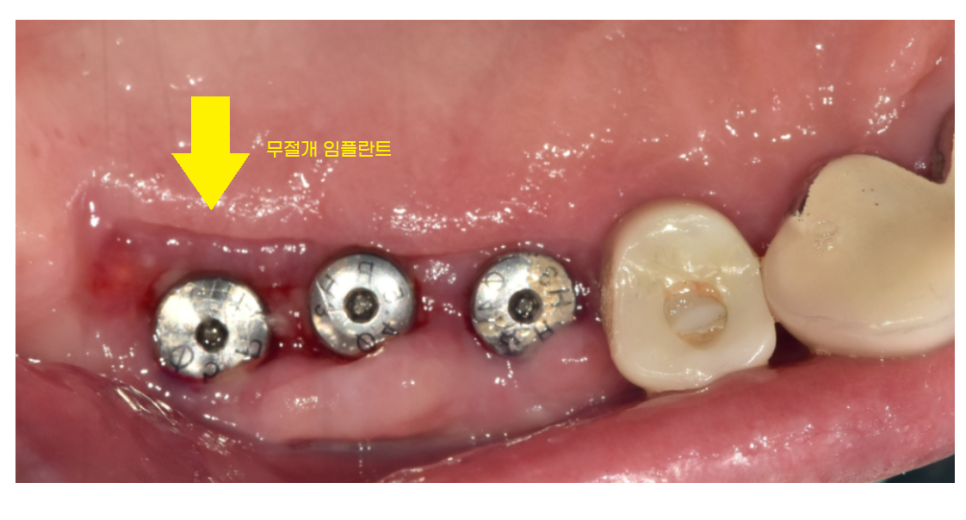

서울 바르디치과의 장점 중 하나는

90% 이상 무절개 임플란트를 시행합니다.

CT를 통해 정확히 분석 후

꼭 필요한 부위만 구멍을 뚫어 수술을 진행하기때문에

불필요한 잇몸절개가 필요없습니다.

230704